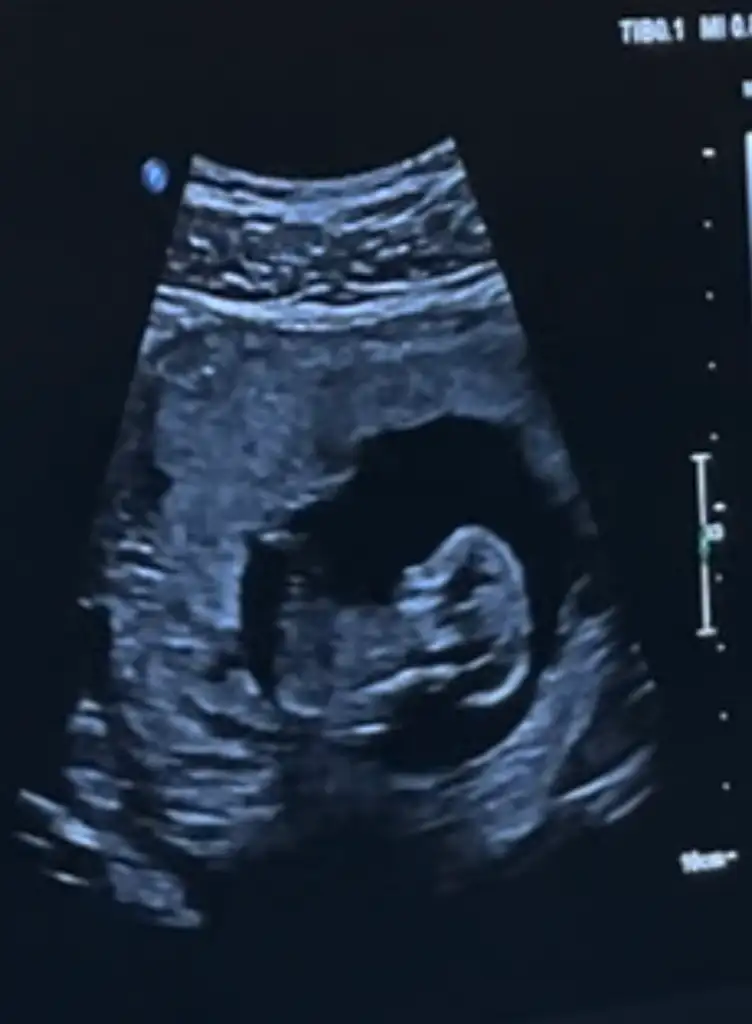

Arkadaşlar lütfen benimkisinde bakarmısınız 12. Haftada erkeğe benziyor dendi bu 12. Haftalık ultrason 16 haftada kız dendi sizce nedir

• CAP_6B9B2076-EB37-4588-9FE9-C2183774154C.webp

16,8 KB · Görüntüleme: 848